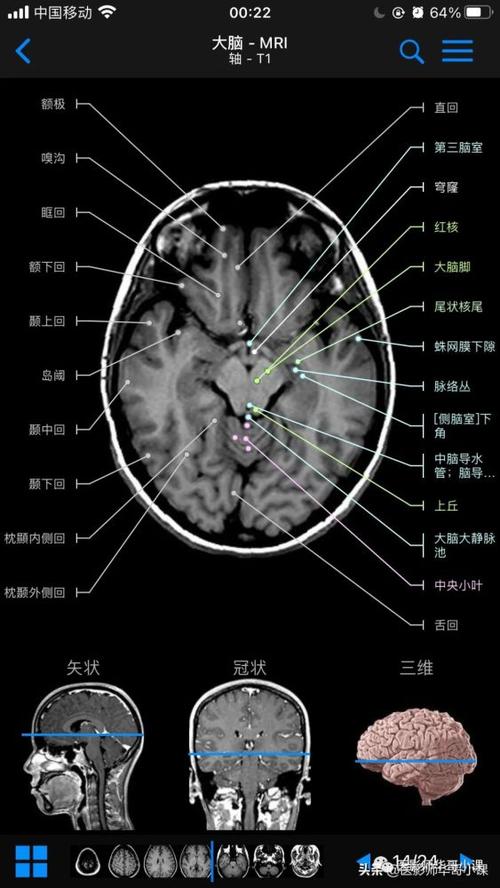

磁共振解剖图

磁共振解剖图,颈椎磁共振图片

【高清mri图】颅脑磁共振mri解剖

头颅磁共振解剖图

磁共振脑干解剖图